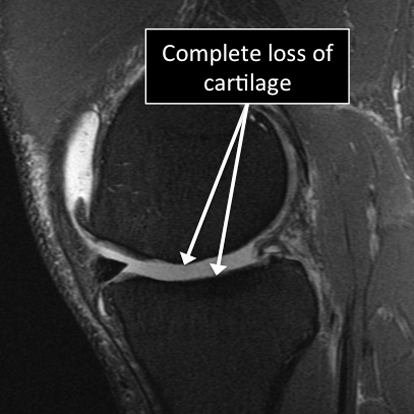

- MRI allows us to see different regions of the cartilage.

- Several injuries or diseases affecting the cartilage can be diagnosed using MRI.

- Common things affecting the cartilage include degenerative or traumatic defects, abnormal calcium deposition in the cartilage, fractures affecting the cartilage and the underlying bone (osteochondral fractures), among others.

Knee MRI examinations showing normal (top) and abnormal (bottom) articular cartilage.